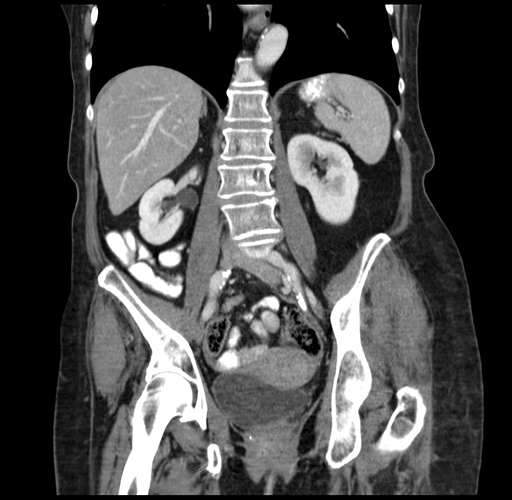

Pre-Chemo: Coronal Venous

Coronal Venous